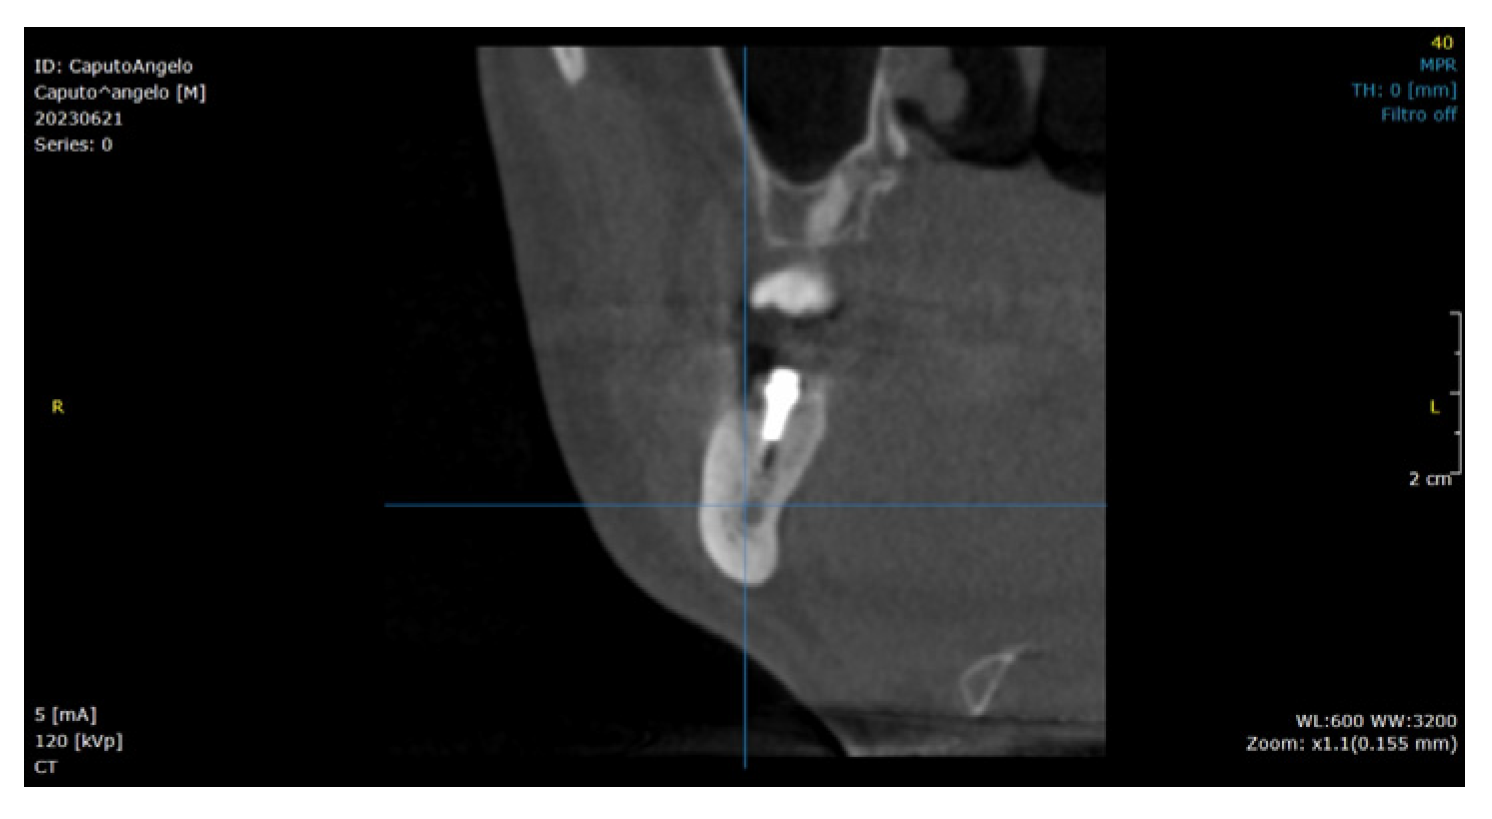

2.2. Surgical Technique